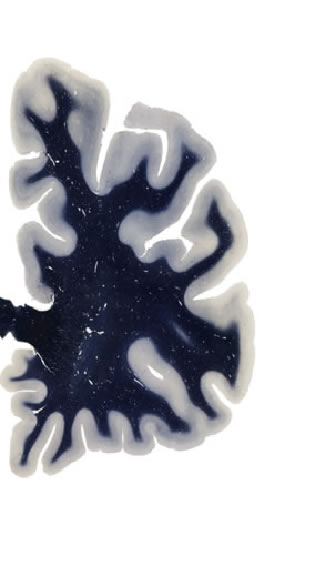

Hi-Resolution Sections · Cells (Nissl Staining) · Virtual Microscopy

Frontal sections (Nissl) from the Atlas Brain:

Slice ID:

r2-0820

Plate NR:

08

Position:

-25,4 mm